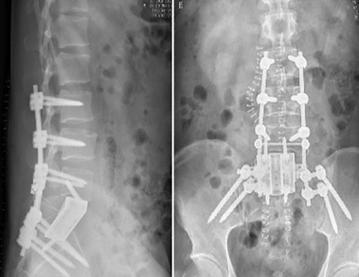

手術在新的一天的淩晨2點結束,術中跟台護士更換了3批,患者翻身2次,曆時10餘個小時,生命體征未出現波動,患者在ICU病房幾小時後即拔管蘇醒。術後的患者如廁正常,並已下地活動,複查X光片,內固定位置良好,假體完全貼合。

第三步再次前路,從腹膜後整塊切除椎體及被腫瘤包繞的右側S1神經根一段,並重新搭橋吻合。植入3D打印個體化適型假體,匹配後鎖釘固定。